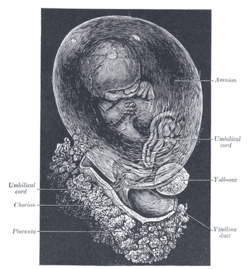

Additional images

Fetus of about 8 weeks, enclosed in the amnion. Magnified a little over two diameters.

Fetus of about 8 weeks, enclosed in the amnion. Magnified a little over two diameters. Picture of freshly delivered placenta and umbilical cord wrapped around Kelly clamps